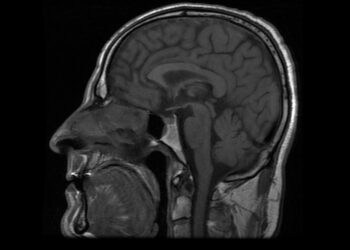

Skaityti daugiauDetailsHipotalaminė hamartoma – tai retas, nuo gimimo esantis darinys, augantis prie vienos iš smegenų sričių, vadinamos hipotalamu. Hipotalamas yra migdolo...